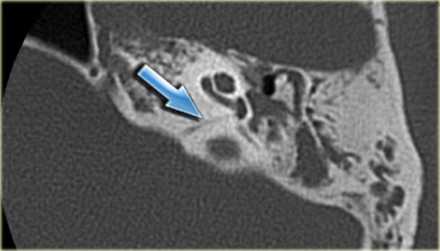

Больная Ф., 30 лет, обратилась с жалобами на головокружение, снижение слуха на правое ухо, слизистое отделяемое из правого уха. Болеет в течение 6 лет, лечилась консервативно. При отомикроскопии визуализируется перфорация в верхнем отделе барабанной перепонки.

Пациентке была выполнена МРТ основания черепа по описанной методике (рис. 1). Рисунок 1. МРТ основания черепа больной Ф. с хроническим правосторонним гнойным средним отитом. Фистула лабиринта. Холестеатома. а — исследование в режиме Т1; б — в режиме Т2; в — в режиме non-EPI DWI.

В режиме Т1 справа определяется образование с низкой интенсивностью сигнала, а в режиме Т2 и non-EPI DWI — образование с гиперинтенсивным сигналом. Диагноз: хронический правосторонний гнойный средний отит; холестеатома; фистула лабиринта. Пациентка была подвергнута санирующей операции на правом ухе с тимпанопластикой и облитерацией паратимпанальных пространств. Были выявлены холестеатома, заполняющая аттик, адитус, антрум, деструкция цепи слуховых косточек, фистула латерального полукружного канала. Послеоперационный период протекал без особенностей, на 15-е сутки была удалена гемостатическая губка и силиконовая выстилка. При контрольном осмотре ухо сухое, отмечает улучшение слуха, головокружения нет. Через 12 мес проведено повторное МРТ-исследование. Признаков холестеатомы не обнаружено. Получен хороший функциональный результат — ухо толерантно к воде, самоочищается.